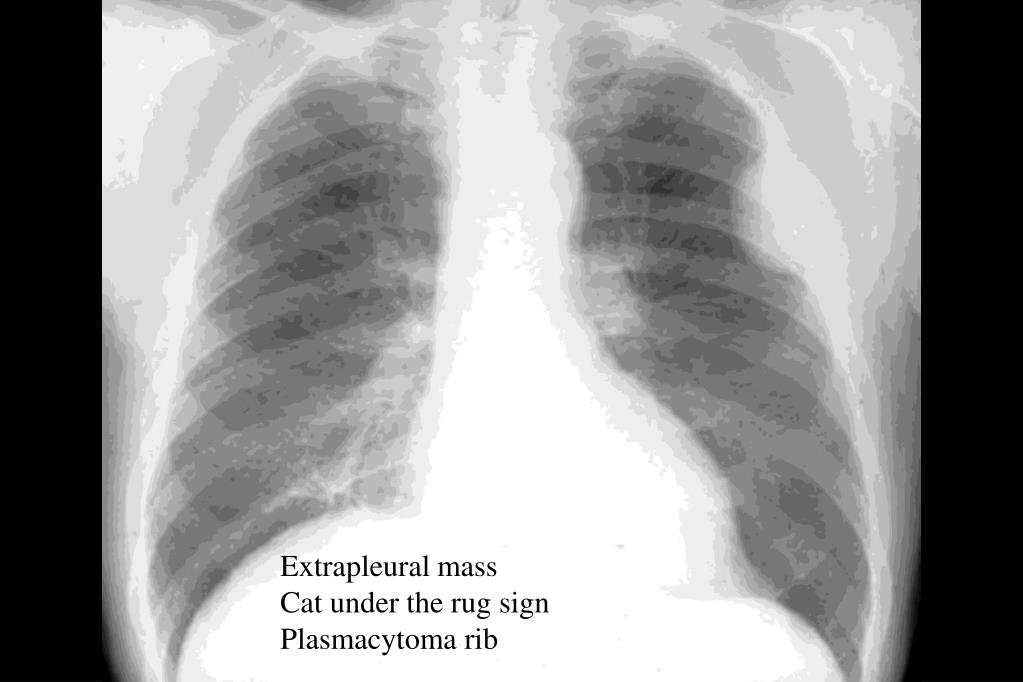

Cat Under The Rug Sign The extrapleural sign refers to the appearance of a pulmonary opacity with oblique. Expanding lesions of structures in the chest wall give rise to this sign. The extrapleural sign refers to the appearance of a pulmonary opacity with oblique. Learn how to recognize the common signs of trauma in cats, such as aggression, hiding, and inappropriate toileting. When you handle your cat, check her paws… she may need a nail trimming. Check out our funny cat saying rug selection for the very best in unique or custom, handmade pieces from our shops. Citation, doi, disclosures and article data. This sign helps to recognize the site of the lesion. Learn why cats do odd things like rolling over, presenting their butt, covering food, eating plastic, and more. You might notice cats climbing under rugs, blankets, and other fabrics in your home to lunge out when they see an oncoming. If she is snagging on the carpet, that might cause her to. You can entice your cat to burrow under blankets by placing treats or toys under the covers, creating a fun and interactive.